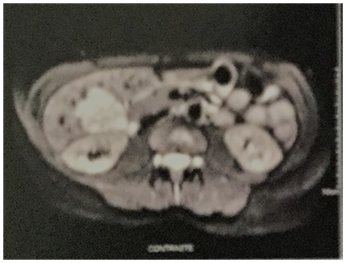

A 32year-old female was referred to us for the appearance of incidental nodular lesion into segment V of the liver. This patient has ever used neither OC’s nor AAS. She reported previous investigation of systemic arterial hypertension over last three months. She presented no familial history for SAH. Secondary arterial hypertension was exhaustively investigated, as renovascular hypertension as adrenal causes like pheochromocytoma and other lesions. All of them were excluded. Neuroendocrine tumors were also excluded since an Octreoscan was negative. Laboratory function tests were within normal limits. Hepatitis B surface, anti-HBs antibody and anti-hepatitis C virus antibody were negative. Serum tumor markers (CEA, CA 19, 9 and α-fetoprotein) were also negative. She presented only seric high levels of both renin (17,9dl/ml) and aldosterone (16,0dl/ml). She used 1500mg/day of methyldopa because she wished to make pregnant. Abdominal computer tomography (CT) showed a hypervascular heterogeneous lesion measuring 40 X 38 X 36mm and localized in V hepatic segment very close from gallbladder (Figure 1). The lesion was well defined showing dyshomogenous density with irregular enhancement in the arterial phase and wash-out in late phase. CT findings suggested hepatic adenoma. Surgical resection was indicated due risk of rupture in pregnancy. The patient was brought to the laparoscopic resection that was performed without intercurrences. A 4cm diameter of heterogeneous hemorrhagic hepatic lesion was observed in V hepatic segment (Figure 2). This lesion was enucleated and taken off by means endobag. The mass appeared as well circumscribed margins lesion with smooth external surface. The lesion was green-brown colored tumor with hemorrhagic areas. Microscopic examination showed the presence of mature, vacuolated hepatocytes; no portal or biliary structures were present, which confirmed inflammatory HA. Lesion presented hemorrhagic focus, but presented no malignant signals. Immuno-histochemistry evaluation showed IL6ST mutation which confirmed inflammatory AH. The patient stayed two days in Hospital. She recovered well without postoperative complications. Following surgery, as seric levels of both renin and aldosterone as arterial pression were decreased. After three months of surgical resection, they presented normal levels and SAH was resolved without use of anti-hypertensive drugs. At last follow-up examination at two years did not reveal the presence of any further focal lesions, and she presents well without SAH. The seric levels of both renin and aldosterone presented normal at last follow-up. This patient has used none anti-hypertensive drug.

Figure 1 Magnetic Nuclear Resonance with gadolinium-Hypervascular heterogeneous lesion localized in V hepatic segment.